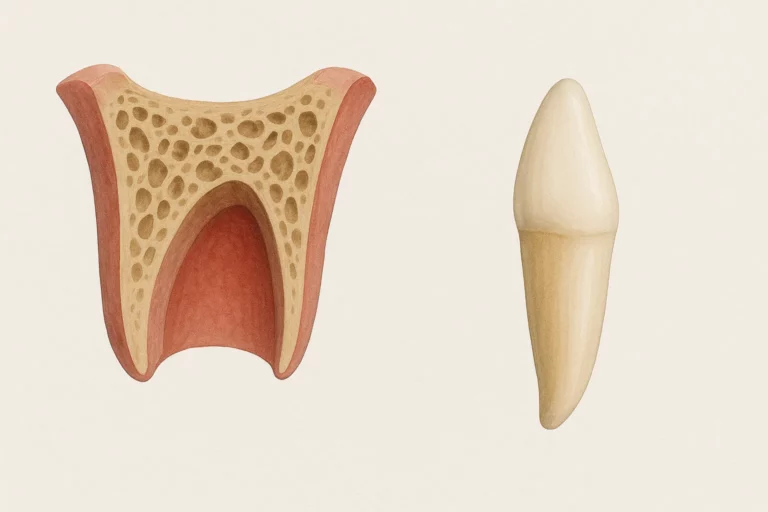

Zwichnięcie zęba to poważny uraz stomatologiczny, przy którym ząb przemieszcza się w obrębie zębodołu, jednak nadal utrzymuje częściowy kontakt z kością wyrostka zębodołowego. W przeciwieństwie do wybicia zęba (avulsji), gdzie dochodzi do całkowitej utraty kontaktu zęba z zębodołem, przy zwichnięciu struktury podporowe zęba pozostają częściowo zachowane – choć często poważnie uszkodzone.

Pourazowe uszkodzenia zębów klasyfikuje się według stopnia uszkodzenia tkanek i kierunku przemieszczenia:

Typy zwichnięć zębów – infografika